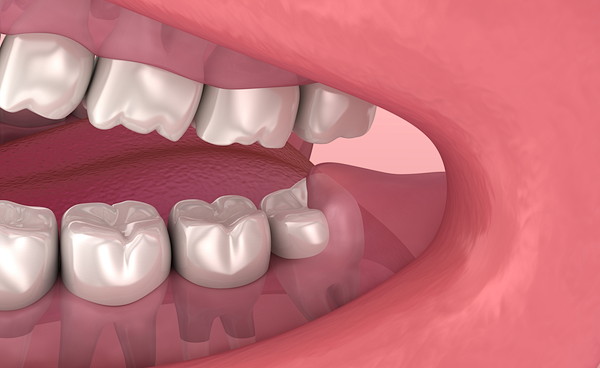

まっすぐ生えているタイプ

ほかの歯と同様にまっすぐ垂直に生えているタイプです。

ほかの歯に悪影響を与えず、上下で噛み合わせている場合、トラブルになる可能性は少ないと考えられています。

ただし、親知らずが上下ともまっすぐに生えてくる可能性は低い傾向にあります。

今は問題なく生えていたとしても、将来的に移動する、磨きにくく汚れがたまって腫れや痛みを繰り返すこともあります。

定期検診の時に親知らずの状態を確認してもらい、問題がないかチェックしてもらいましょう。

残すことができる親知らずは、適合に条件はありますが、歯の移植に使うことができる場合があります。

将来奥歯を失った際に、親知らずを移植できる選択肢が残っていると、治療の幅が広がります。

まっすぐ生えていて、腫れや痛みなどのトラブルがない歯は、保存しておくことがおすすめです。